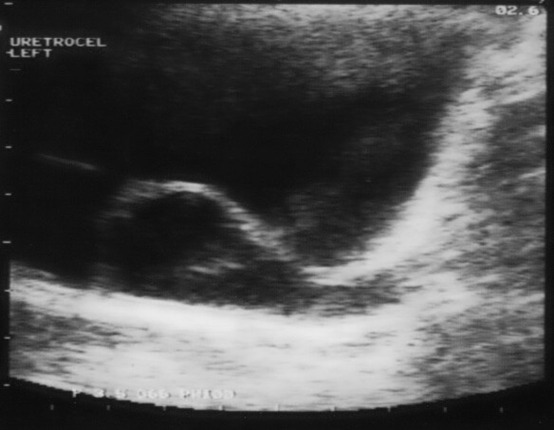

📌التصوير بالموجات الفوق صوتية